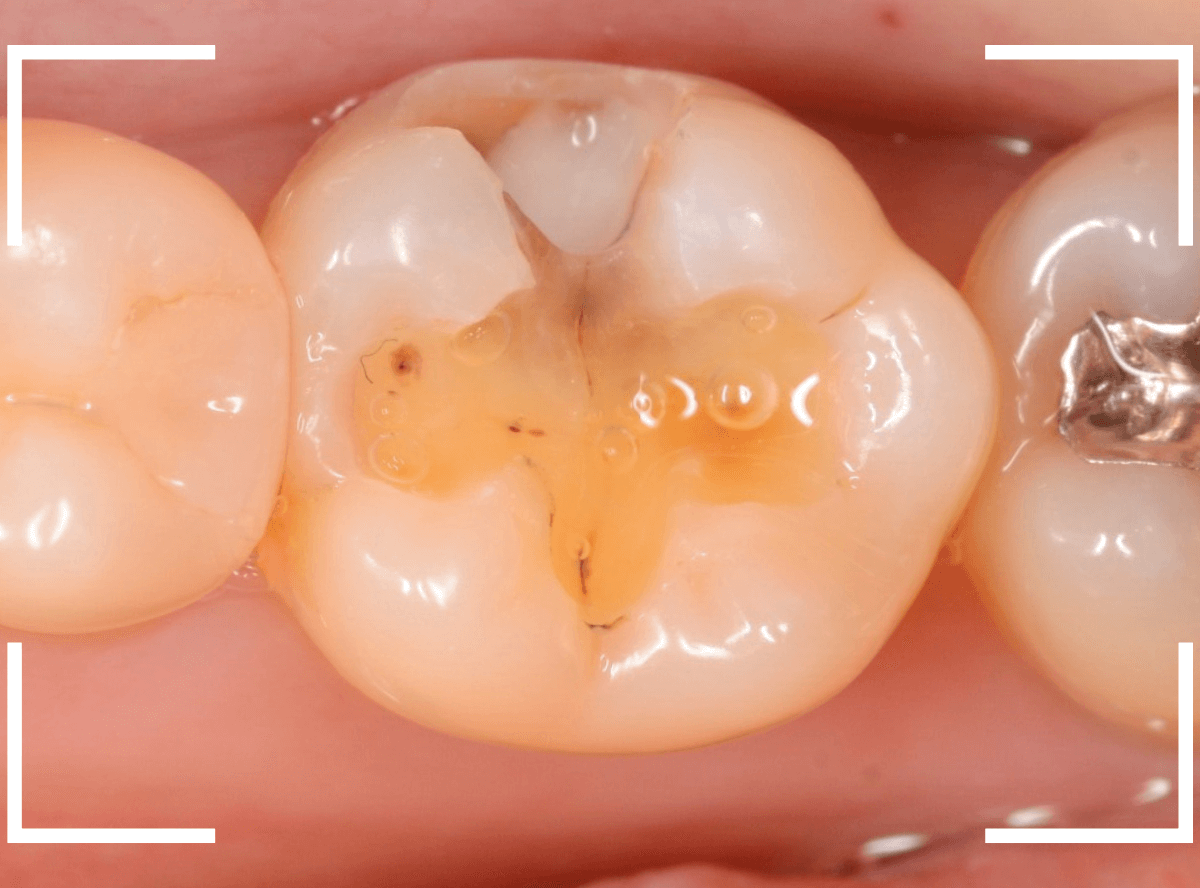

Case.3 レジンの下で神経に触れそうなほどの虫歯

こちらは、下の奥歯の写真です。

特に症状の訴えはありませんでしたが、

歯を観察した瞬間、「虫歯がありそうだな」と思われるような所見です。

私の目には大体このように映っています。

レントゲン写真です。

私が虫歯っぽいと思っていた部分よりも、むしろ手前の部分に大きな虫歯がありました。

もう神経に触りそうな大きな虫歯です。

これだけの虫歯であれば、通常であれば、歯がしみたり、食事中に痛みがあったり何らかの症状があるのですが、無症状のこともあります。

麻酔をして治療開始です。

少し削ると、大きな虫歯が出てきました。

手前の歯にもかかる大きな虫歯でした。

ここまで削っても、まだ、虫歯が残っています。

すぐ下には歯の神経が来ていますから、より慎重に虫歯を除去します。

露髄(歯の神経が見えてしまう事)に怯えながら、慎重に虫歯を除去しました。

なんとか神経ギリギリのところで虫歯がとどまっていました。

虫歯を完全に除去した後、お薬とセメントをつめて経過観察です。

かなり大きな虫歯でしたが、おそらく神経の治療をせずになんとかなりそうです。。。